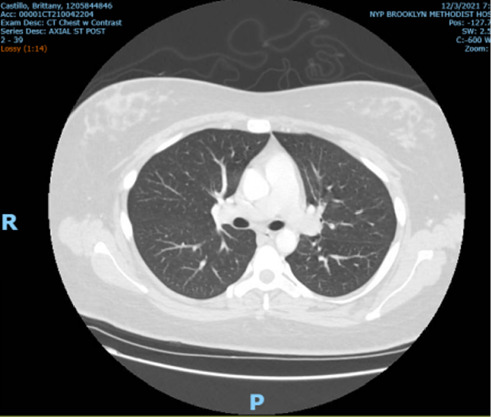

Abstract Image